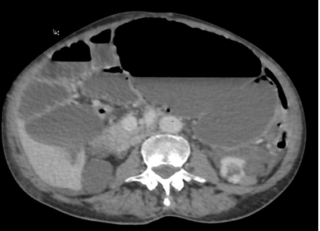

Figure 2 : Image scanographique montrant un cæcum distendu et basculé au niveau de l’hypochondre gauche.

Scanner abdominal (TDM) :

Le scanner a révélé une distension de l’intestin grêle située en amont de deux « signes du bec » (beak signs) contigus. Ce tableau clinique est compliqué par un volvulus du cæcum par torsion, avec la présence caractéristique d’une image en tourbillon (whorl sign), sans que des signes de complications majeures ne soient visibles à ce stade.